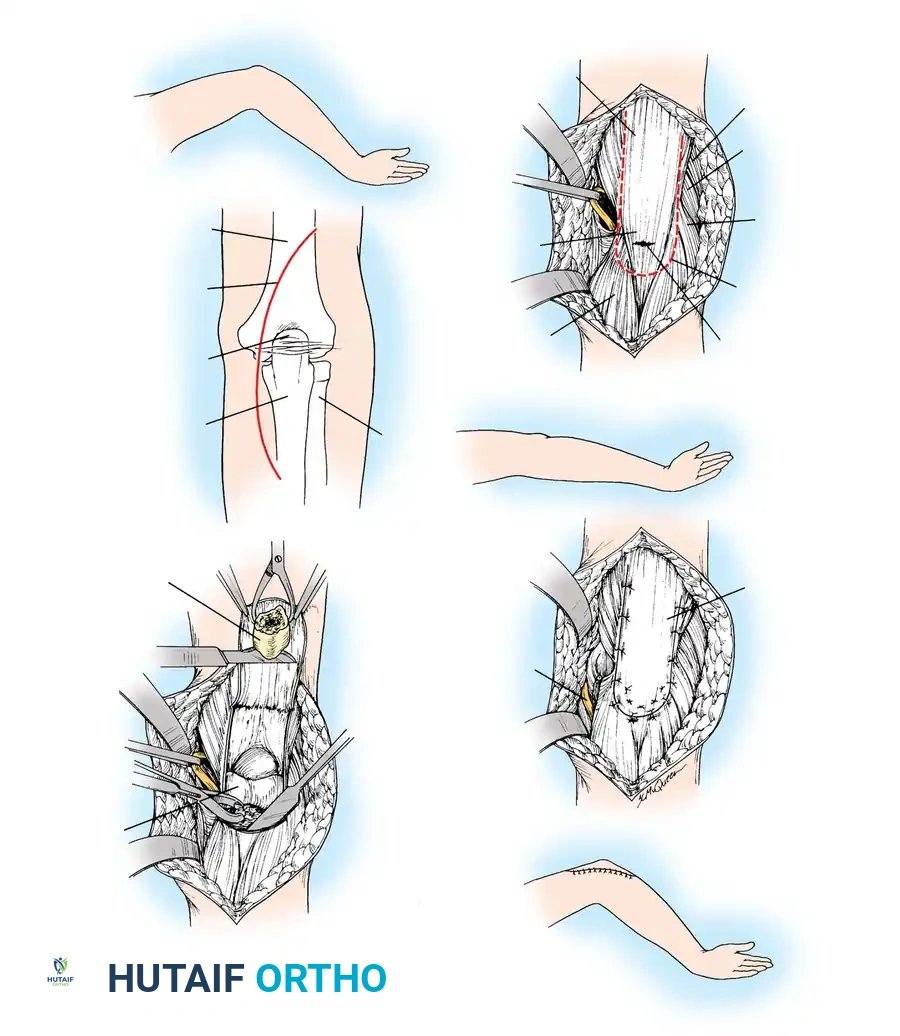

The Posterior Approach

- Make a longitudinal incision beginning 2.5 cm proximal to the tip of the olecranon.

- To avoid a painful scar directly over the bony prominence, curve the incision slightly lateral to the tip of the olecranon, then continue it distally along the subcutaneous border of the ulnar shaft for 7.5 cm.

- Incise the deep fascia in line with the skin incision.

- Identify and protect the ulnar nerve, particularly if the fracture extends medially or if plate fixation is planned. Routine transposition is not required unless the nerve is involved in the fracture site or hardware placement threatens it.

🔪 Surgical Technique: Tension Band Wiring

- Exposure: Expose the fracture site and clear the joint of hematoma and small osteochondral debris.

- Drill Hole: Drill a transverse hole from side to side in the distal ulnar fragment, approximately 2 to 3 cm distal to the fracture line. Ensure the hole is deep enough to avoid cutting through the posterior cortex.

- Wire Passage: Pass an 18-gauge (1.2 mm) stainless steel wire through the drill hole.

- Proximal Purchase: Pass the wire beneath the aponeurosis of the triceps muscle, directly adjacent to the bone, and around the tip of the olecranon. Alternatively, a transverse drill hole can be made in the proximal fragment if it is large enough.

- Figure-of-Eight: Carry one end of the wire obliquely across the posterior aspect of the fracture to the opposite side. Cross the other end over it to create a figure-of-eight configuration.

- Reduction and Compression: While an assistant grasps the proximal olecranon fragment with a large towel clip and exerts distal traction to anatomically reduce the fracture, twist the wire loop tightly.

Fig. 54-54 Internal fixation of olecranon with tension band wire loop. Wire passed through hole drilled in distal fragment and through triceps aponeurosis adjacent to bone. Figure-of-eight loop adds stability to fracture and prevents distraction and posterior bowing.

🔪 Surgical Technique: Excision and Triceps Advancement

- Fragment Removal: Carefully dissect the comminuted fragments from the triceps tendon, preserving as much tendon length as possible.

- Joint Debridement: Inspect the joint and remove all intra-articular debris.

- Bone Preparation: Smooth the remaining proximal end of the ulna. If the midportion of the olecranon is comminuted but the proximal tip is intact, the central comminuted segment can be excised (Barford technique). The osteotomies must be directed accurately along the radius of the trochlear curve to reconstitute a smoothly curved notch.

- Triceps Advancement: Drill two or three longitudinal holes through the remaining proximal ulna. Pass heavy non-absorbable sutures (e.g., #2 or #5 FiberWire) through the triceps tendon using a Krackow stitch, pass them through the drill holes, and tie them securely over the posterior ulnar cortex with the elbow in 30 degrees of flexion.